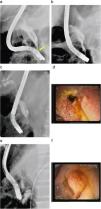

Figura 2. a) Estenosis de colédoco distal filiforme secundario a su pancreatitis crónica (flecha) con conducto cístico de implantación baja. Páncreas dorsal rellenado desde la papila minor (cabeza de flecha). b) Dilatación con balón de alta presión de 6mm de diámetro. c) Estenosis de 20mm de longitud en el colédoco distal con un calibre de menos de 2mm y dilatación de la vía biliar supraestenótica de 12mm. d) Prótesis migrada hacia colédoco; viéndose sólo parte de la malla metálica en el borde superior de la papila mayor. e) Prótesis metálica de 10×40mm que ha migrado hacia el colédoco. f) Papila mayor con tejido de granulación 2 meses después.

A los 2 meses, se realizó una nueva CPRE para valorar el recambio de la prótesis. Se pudo constatar que la prótesis había migrado hacia el colédoco, de tal manera que sólo se veía parcialmente la prótesis en la parte superior de la papila (figura 2d). En la imagen radiológica, se pudo comprobar la migración de la prótesis (figura 2e). Se intentó despegar la prótesis con asa de polipectomía, pinza de 3 patas, pinza de cuerpos extraños, pinza de biopsias, papilotomo con guía y luego mediante dilatación con balón entre la prótesis y el colédoco, sin que se consiguiera un resultado eficaz. Tras estas maniobras, se decidió introducir un balón de dilatación hidrostático dentro de la prótesis (CRE™ Wireguided 12-13,5-15mm Esophageal/Pyloric/Colonic 240cm, Boston Scientific Microvasive, Cork, Ireland), hincharlo a 3 atmósferas, traccionar de la prótesis hasta conseguir despegar la prótesis del colédoco y sacarla parcialmente al duodeno. Ahora, se extrajo con facilidad la prótesis mediante una pinza de cuerpos extraños.

A los 2 meses se revisaron el duodeno y el colédoco, y se encontró tejido de granulación en la zona donde se había adherido la prótesis (figura 2f) y un calibre de la estenosis muy superior a otras técnicas que alcanzaba los 8mm . Durante su seguimiento en 6 meses, presentó una bioquímica hepática normal sin evidenciar dilatación de la vía biliar mediante ecografía.